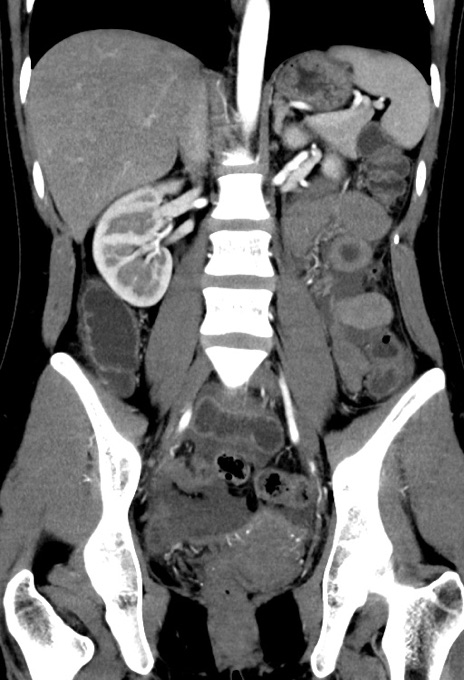

症例17(冠状断像)

【症例】20歳代女性

【主訴】嘔吐、下腹部痛

【現病歴】昨日夕食後に嘔吐し下腹部痛が出現。本日になっても嘔吐持続し改善しないため来院。

【身体所見】意識清明、BT 37.2℃、BP 108/67mmHg、腹部:平坦、やや硬、下腹部正中から右にかけて圧痛あり、反跳痛軽度あり、tapping pain(+)。

【データ】WBC 13600、CRP 14.94